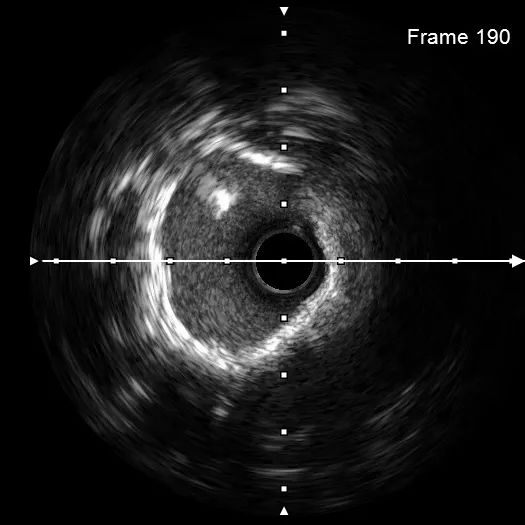

主干末端POT,提示支架内膨胀不全(偏心,下图一蜘蛛位扩张满意,下图二肝位扩张不全,下图三肝位复查造影提示支架膨胀不全)。

此时要选择腔内影像指导?但超选已明确为支架膨胀不良。虽为主干支架,但目前左冠血流TIMI-III级,已达急诊目的,拟充分抗栓下选择Shockwave血管内冲击波导管处理。

遂采用3.5*12mm Shockwave IVL导管于钙化狭窄处精准治疗。IVL导管充分排气后,送至支架内钙化病变部位,充盈1:1造影剂盐水,并扩张至4atm,按动IVL连接手柄按键,一键启动血管内冲击波发放,每秒1次脉冲,每10个脉冲为一组;每组血管内冲击波治疗后,回抱IVL球囊,以充分排出“震波”剩余气泡,避免能量损失。再将导管扩张至4atm。进行下一组血管内冲击波治疗。过程中,可见IVL球囊充盈缺损逐渐消失,直观展现了斑块重塑、血管松解。

最终,共进行3次血管内冲击波治疗后,复查原支架膨胀不良处可见膨胀改善。